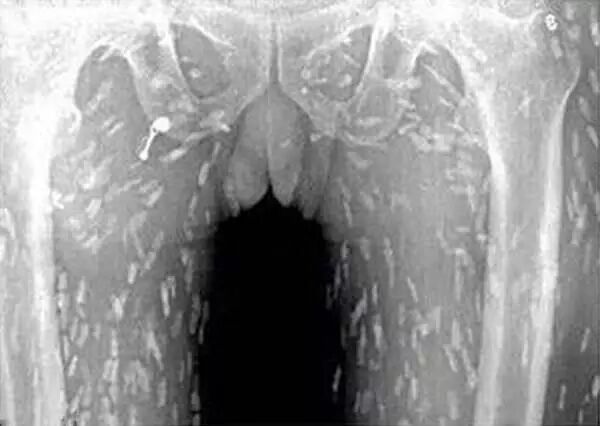

根据英国媒体报导,去年有位广州的男子,非常爱吃生鱼片,有天感到全身皮肤奇痒无比又疼痛难耐,到医院检查照了X光后发现,他整个胸腔体内布满寄生虫,追问下才知道他常吃生鱼片,而且有可能吃入很多受污染的生鱼片。

幸好这名广州男子在感到皮肤搔痒时就诊治疗,及早发现寄生虫的问题。不要以为活跳跳的鲜鱼就不会有寄生虫,寄生虫和生鱼的新鲜程度并没有直接关系。每隻鱼捕上岸都会带有很多寄生虫,那么该如何吃,才能品尝到生鱼片的美味,又不会寄生虫缠上身呢?